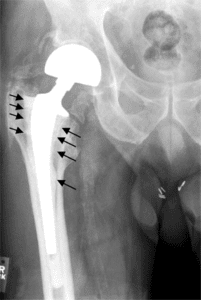

In collaboration with Johnson & Johnson, the DePuy Orthopedics developed a device in 2005 which sought to alleviate issues brought on by hip degradation. The DePuy ASR XL Acetabular System consists of a ball and joint mechanism made of material such as chromium and other materials that have been shown to withstand constant movement and rotation over the years.

The DePuy device was found to have several defects shortly after its launch, given its rate of failure. It was shown that the device could disintegrate over time and even move from one part of the leg to a different section (metallosis). This can lead to issues such as tissue necrosis and a host of nervous system disorders.

By 2008, the FDA had already started receiving reports of the medical device failing, a year before the company manufacturing it decided to stop selling it. In 2010, DePuy released a statement which said that the device has a higher than usual failure rate garnered from information collected in Australia by other patients who had had it implanted into them.